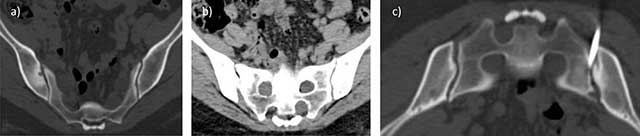

Figure 13

Inflammatory arthritis of the right SI joint of the postpartum in a 36-year-old woman with elevated ESR. Axial CT images in bone a) and soft tissue b) Algorithm: subchondral bone erosions and condensation of the inferior part of the right SI joint with no soft tissue swelling. CT-guided biopsy did not show any evidence of infection.